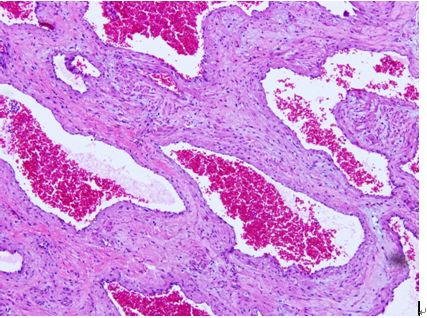

HE染色

1. 脫蠟復(fù)水: 石蠟切片經(jīng)二甲苯Ⅰ、Ⅱ脫蠟各5min,然后放入100%、95%、90%、80%、70%各級(jí)酒精溶液中各3-5min,再放入蒸餾水中3min。

2. 染色:切片放入蘇木精中染色約10-30min。

3.水洗:用自來水流水沖洗約15min。使切片顏色變藍(lán)(或放入堿性水中也可),但要注意流水不能過大,以防切片脫落。

4.分化:將切片放入1%鹽酸乙醇液中褪色,約2秒至數(shù)十秒鐘。見切片變紅,顏色較淺即可。

5.漂洗:切片再放入自來水流水中使其恢復(fù)藍(lán)色。

6.脫水Ⅰ:切片入50%乙醇→70%乙醇→80%乙醇中各3-5min。

7、復(fù)染:用0.5%伊紅乙醇液對(duì)比染色1-3min。

8.脫水Ⅱ:將切片放入95%乙醇中洗去多余的紅色,然后放入無水乙醇中3-5min。最后用吸水紙吸干多余的乙醇。

9.透明:切片放入二甲苯Ⅰ、Ⅱ中各3-5min。

10.封藏:中性樹膠封存